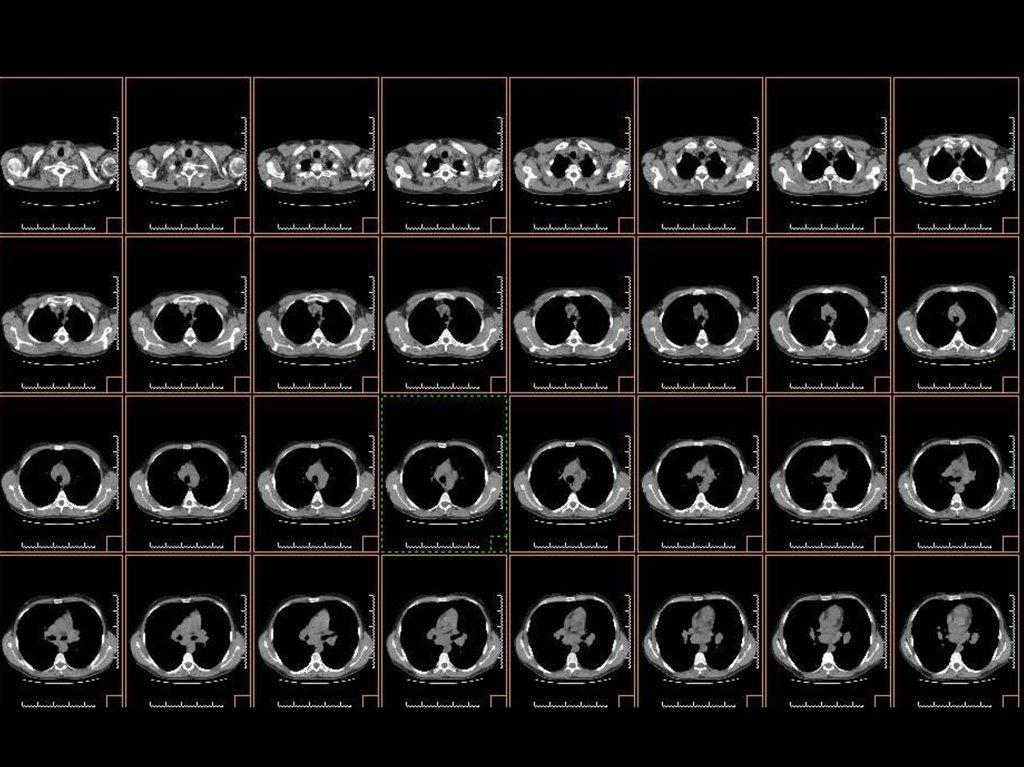

исследование лёгких

Ток: 50 мА

Напряжение: 140кВ

Толщина среза: 2.5 мм

Матрица: 512х512

Режим: пошаговый